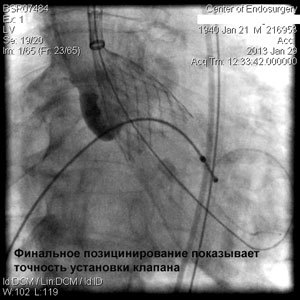

Эта технология - имплантация аортального клапана с помощью маленького разреза (или без него) на бедре, а это значит без вскрытия грудной клетки и кардиохирургической операции!

Через прокол (или маленький разрез) в артерии, в сжатом состоянии проводят искусственный клапан, который расширяется при его установке на месте поврежденного аортального клапана. После раскрытия клапан начинает функционировать и восстанавливает полноценную и нормальную работу аорты.

Впервые в России частная многопрофильная клиника «Центр эндохирургии и литотрипсии», опираясь только на собственные ресурсы и не расходуя бюджетные средства на здравоохранение, выполнила эту уникальную и высокотехнологическую операцию у двух пациентов в возрасте 74 и 82 года.